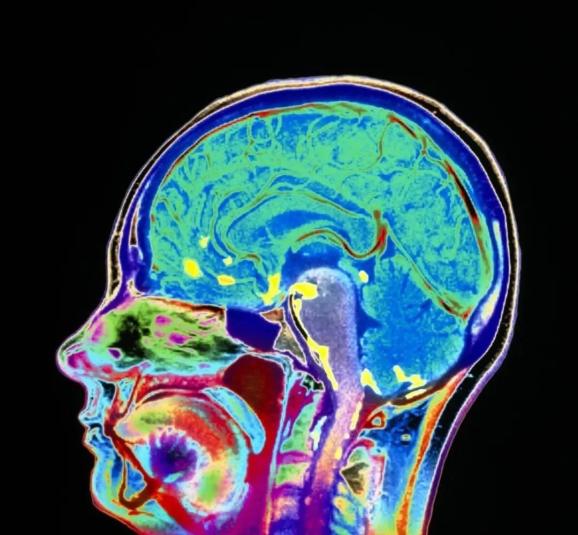

2.确诊困难

脑膜转移患者临床表现缺乏特异性,有时候会误认为是其他神经系统问题,一般来说,增强MRI是发现脑实质转移病灶的首选影像检查。但脑膜转移有时在增强磁共振中没有任何发现,确诊需要进行腰椎穿刺,抽脑脊液检查,脑脊液中找到恶性肿瘤细胞才可以确诊。